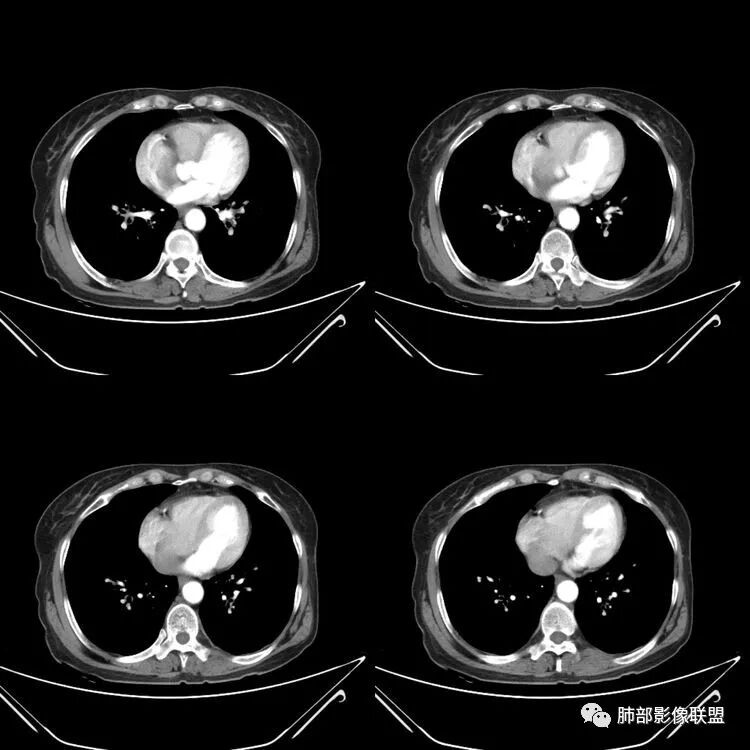

患者,女,64岁,反复咳嗽、咳痰、胸闷10年,加重2周。气管支气管及两肺下叶 支气管弥漫性的环状增厚,管腔扩张,管腔感觉比较松弛。第一感觉,气管支气管淀粉样变。鉴别诊断,1、支气管内膜结核,肺内散在一些支气管的播散病灶,粟粒结节为主,形态比较单一。2、复发性的多软骨炎,就得了解一下其他部位,有没有多个部位的软骨炎。这个病人右侧胸廓缩小,升主动脉明显的扩张,其横径明显的超过了降主动脉。

征象很明确

弥漫支气管壁增厚,膜部受累

声带肥厚——受累

隐约见钙化

南边:肺部有肺气肿支气管腔狭窄淀粉样变性?复发性多软骨炎?血管炎?慢支?结核?曲霉菌?南边:一般还是淀粉样变性与复发性多软骨炎鉴别其次就是支气管骨化症,但是骨化下朝上,且壁结节状钙化明显,本例不太支持。至于结核、曲霉菌?1.结核,一般不会这么广泛,支气管壁狭窄后扩张2.曲霉菌可以这么广泛,但是支气管壁管腔扩张,而且附近脂肪间隙有炎性反应,不太支持;3.血管炎,一般合并肺内有病灶,但是声带受累,放待排;4.软骨炎一般全身受累,例如耳廓等;而且膜部不受累,不太支持;倾向于淀粉样变性;淀粉分很多型,气管支气管是最常见的。尘缘:影像上生理性钙化与支气管骨化无法区别,镜检也不好鉴别,需要依赖活检,看粘膜中是否合并炎性改变(淋巴细胞,组织细胞等炎性细胞侵润)来鉴别Coke with ice:经常看到的这种是老年性肺改变,又称年龄相关肺改变。气管和支气管弥漫性软骨钙化,常见老年女性。尘缘:支气管骨化症很罕见的,所以绝大多数还是生理性钙化。对于老年人,无临床症状的钙化,还是基本上都是生理性钙化,无临床意义。大雄:如果管壁钙化伴明显增厚 影像还是提示一下建议支气管镜稳妥些

病理结果:肺淀粉样变

气管支气管淀粉样变性

三、影像表现

1.气管支气管型

①气管支气管壁增厚,形成粘膜下斑块与结节

②管腔广泛狭窄、闭塞

③管壁钙化

④膜部受累(具有重要鉴别意义)